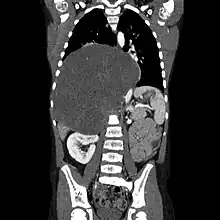

CT scan of a large ganglioneuroma within the chest cavity

Ganglioneuromas can be diagnosed visually by a CT scan, MRI scan, or an ultrasound of the head, abdomen, or pelvis. Blood and urine tests may be done to determine if the tumor is secreting hormones or other circulating chemicals. A biopsy of the tumor may be required to confirm the diagnosis.[4]